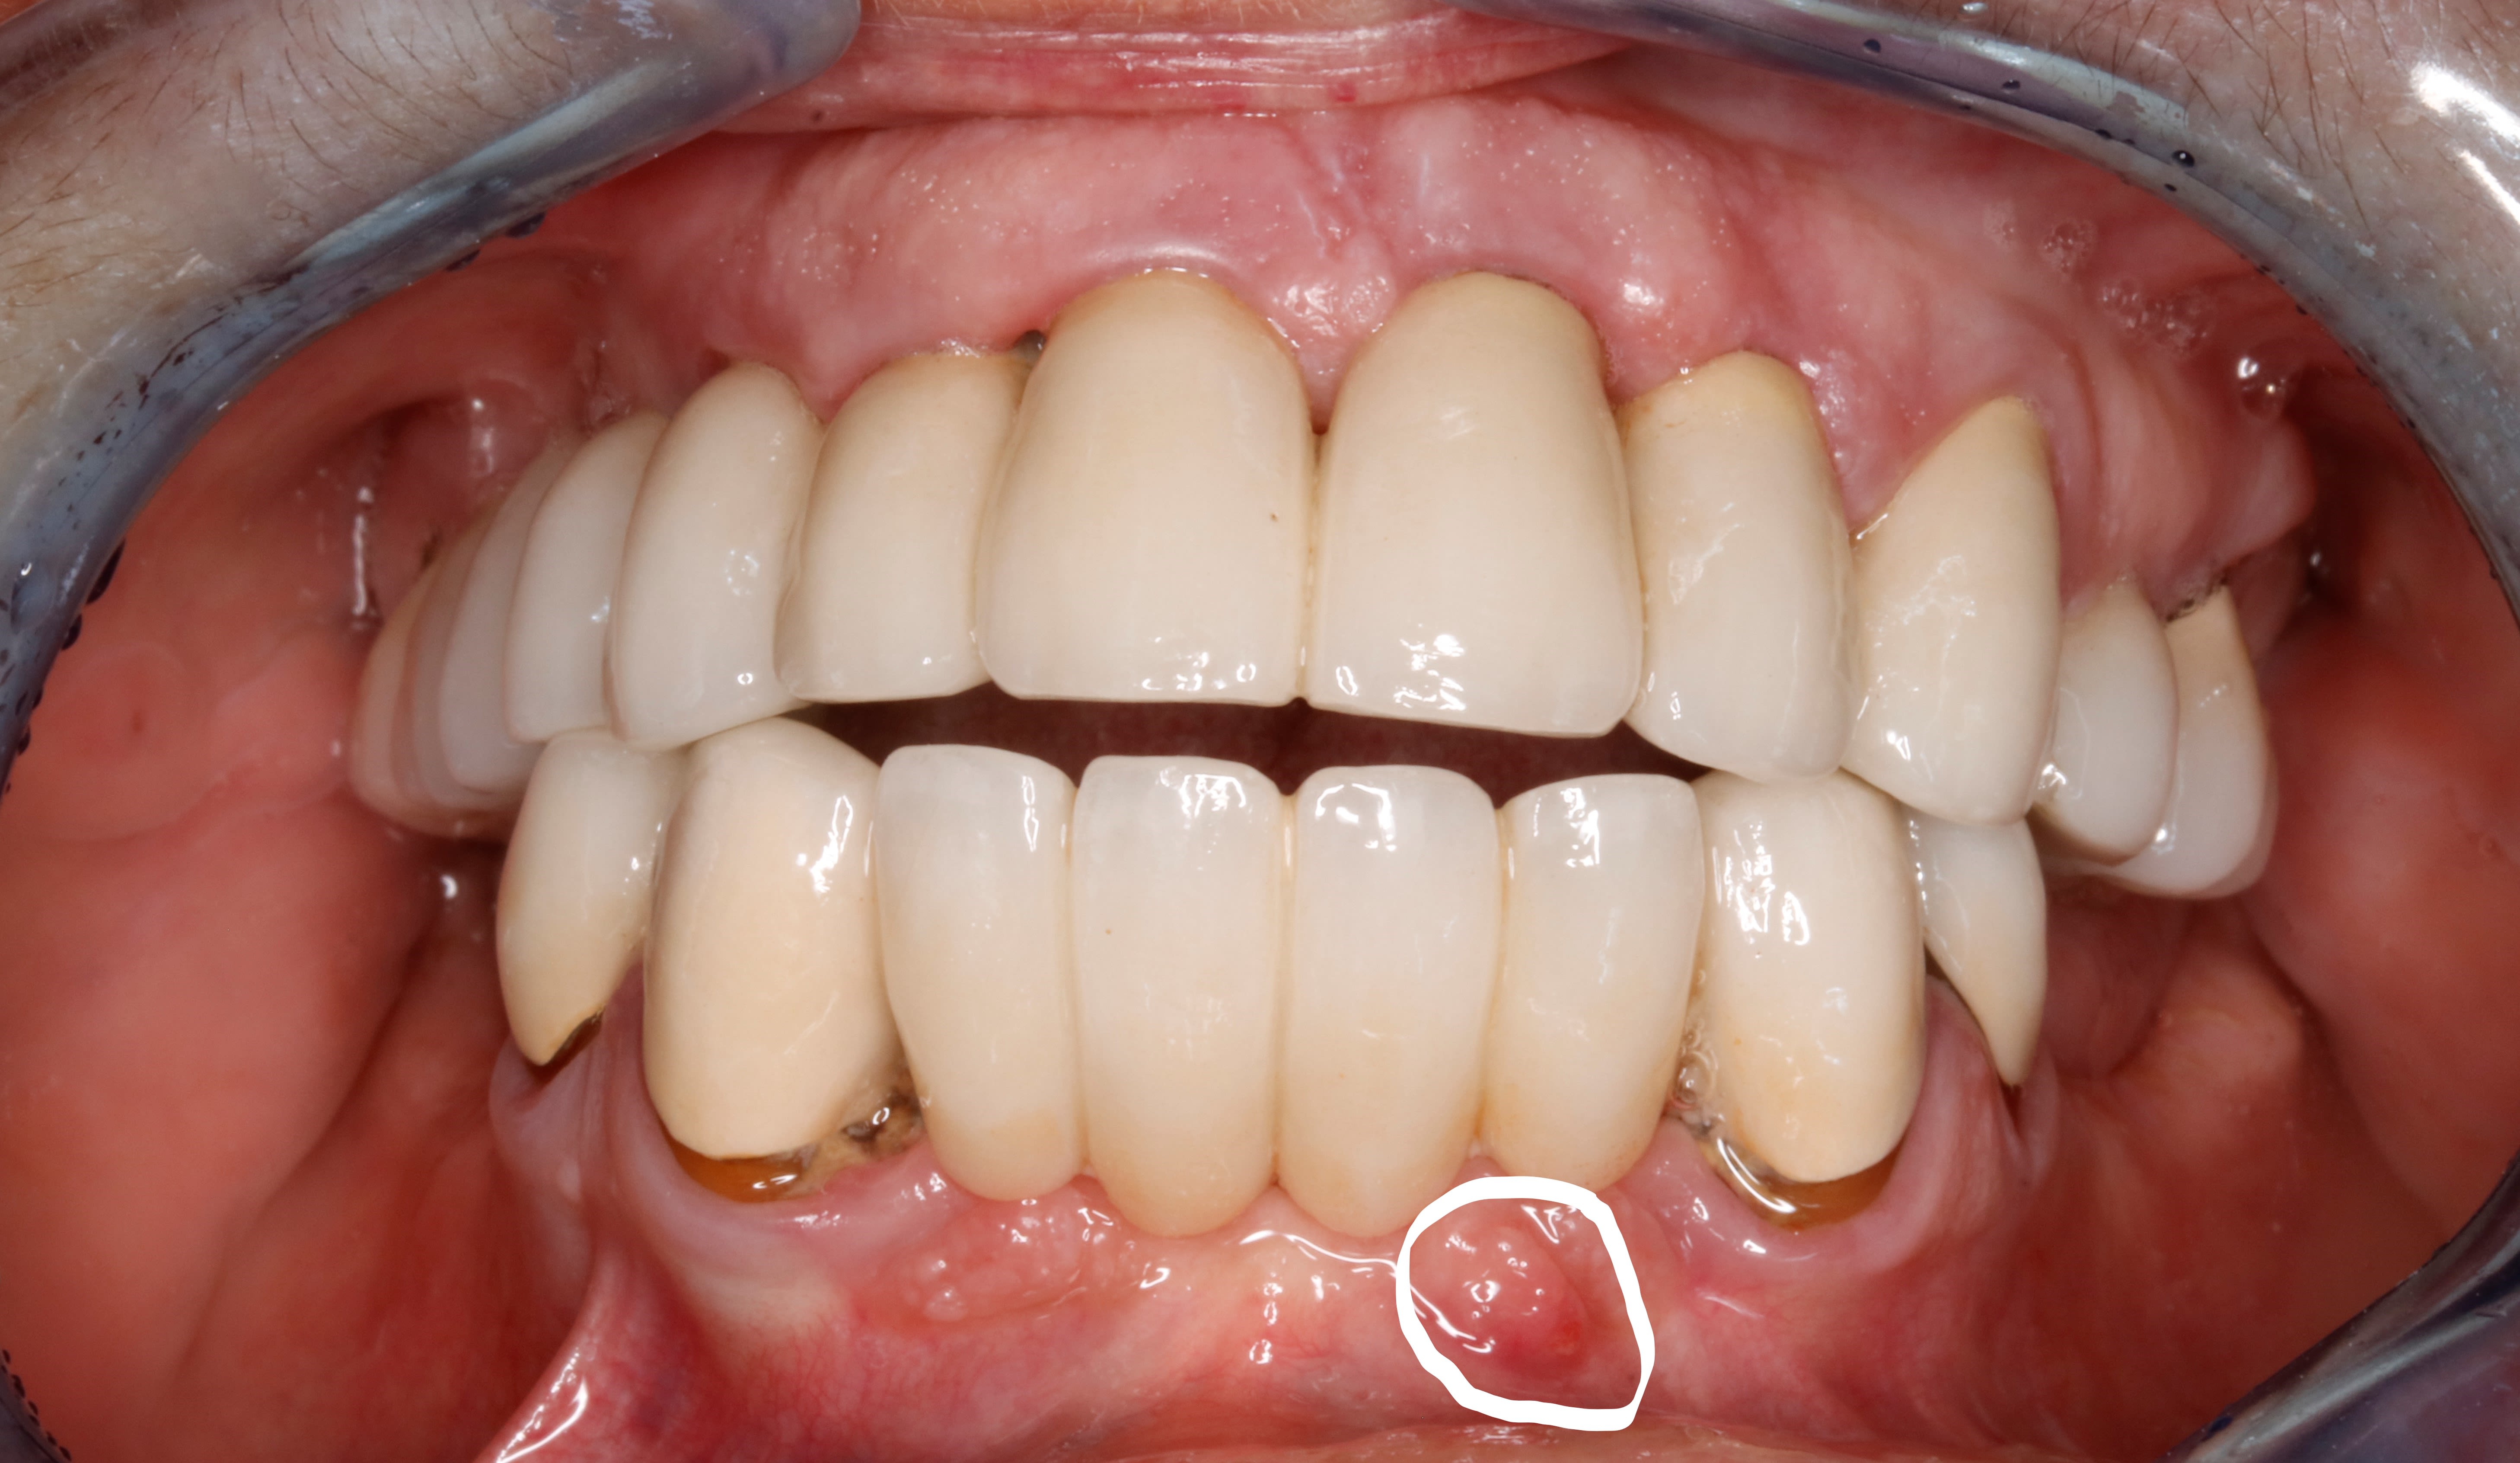

de face .

hummmm d un point de vue paro , j aurais peut etre du extraire la 12

mais sinon , globalement , vu d ou on est parti , et vu l hygiène de vie et hygiène tout court ,

10 ans apres on s en sort bien !

petites caries sous 33 et 43 à machiner

Tu as regardé là? C'est pas homogène.

oui et de l autre coté , aussi . tu penses à quoi ?

Je sais pas... l'autre côté c'est rien je pense.

Là il y a peut être un truc, ou eu un truc.

De ce que l'on voit 🤔 il y avait pas il y a 10 ans.